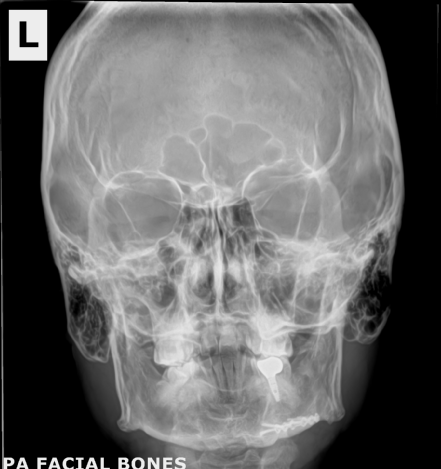

The story of how I got the x-ray or at least the whole scenario was kind of funny. I broke my pinky somehow at my friend's house in Oklahoma in the fall of 2023. When I went to the doctor they did an x-ray of my hand. I have a few metal parts in my head and then told them I got into a fight and thought I may have hurt some implants in my head. Not really but I just wanted these X-rays.